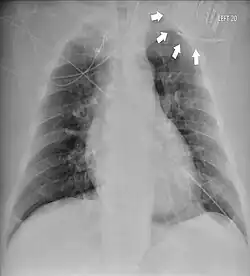

| Chest radiograph showing twiddler's syndrome. The leads of the automated external defibrillator are wrapped around the device and can't be seen in the ventricle. | |

Given its speed and ability to provide a clear image of the lead coiling and device rotation, the chest X-ray is the most straightforward and important diagnostic tool for Twiddler's syndrome.[3]